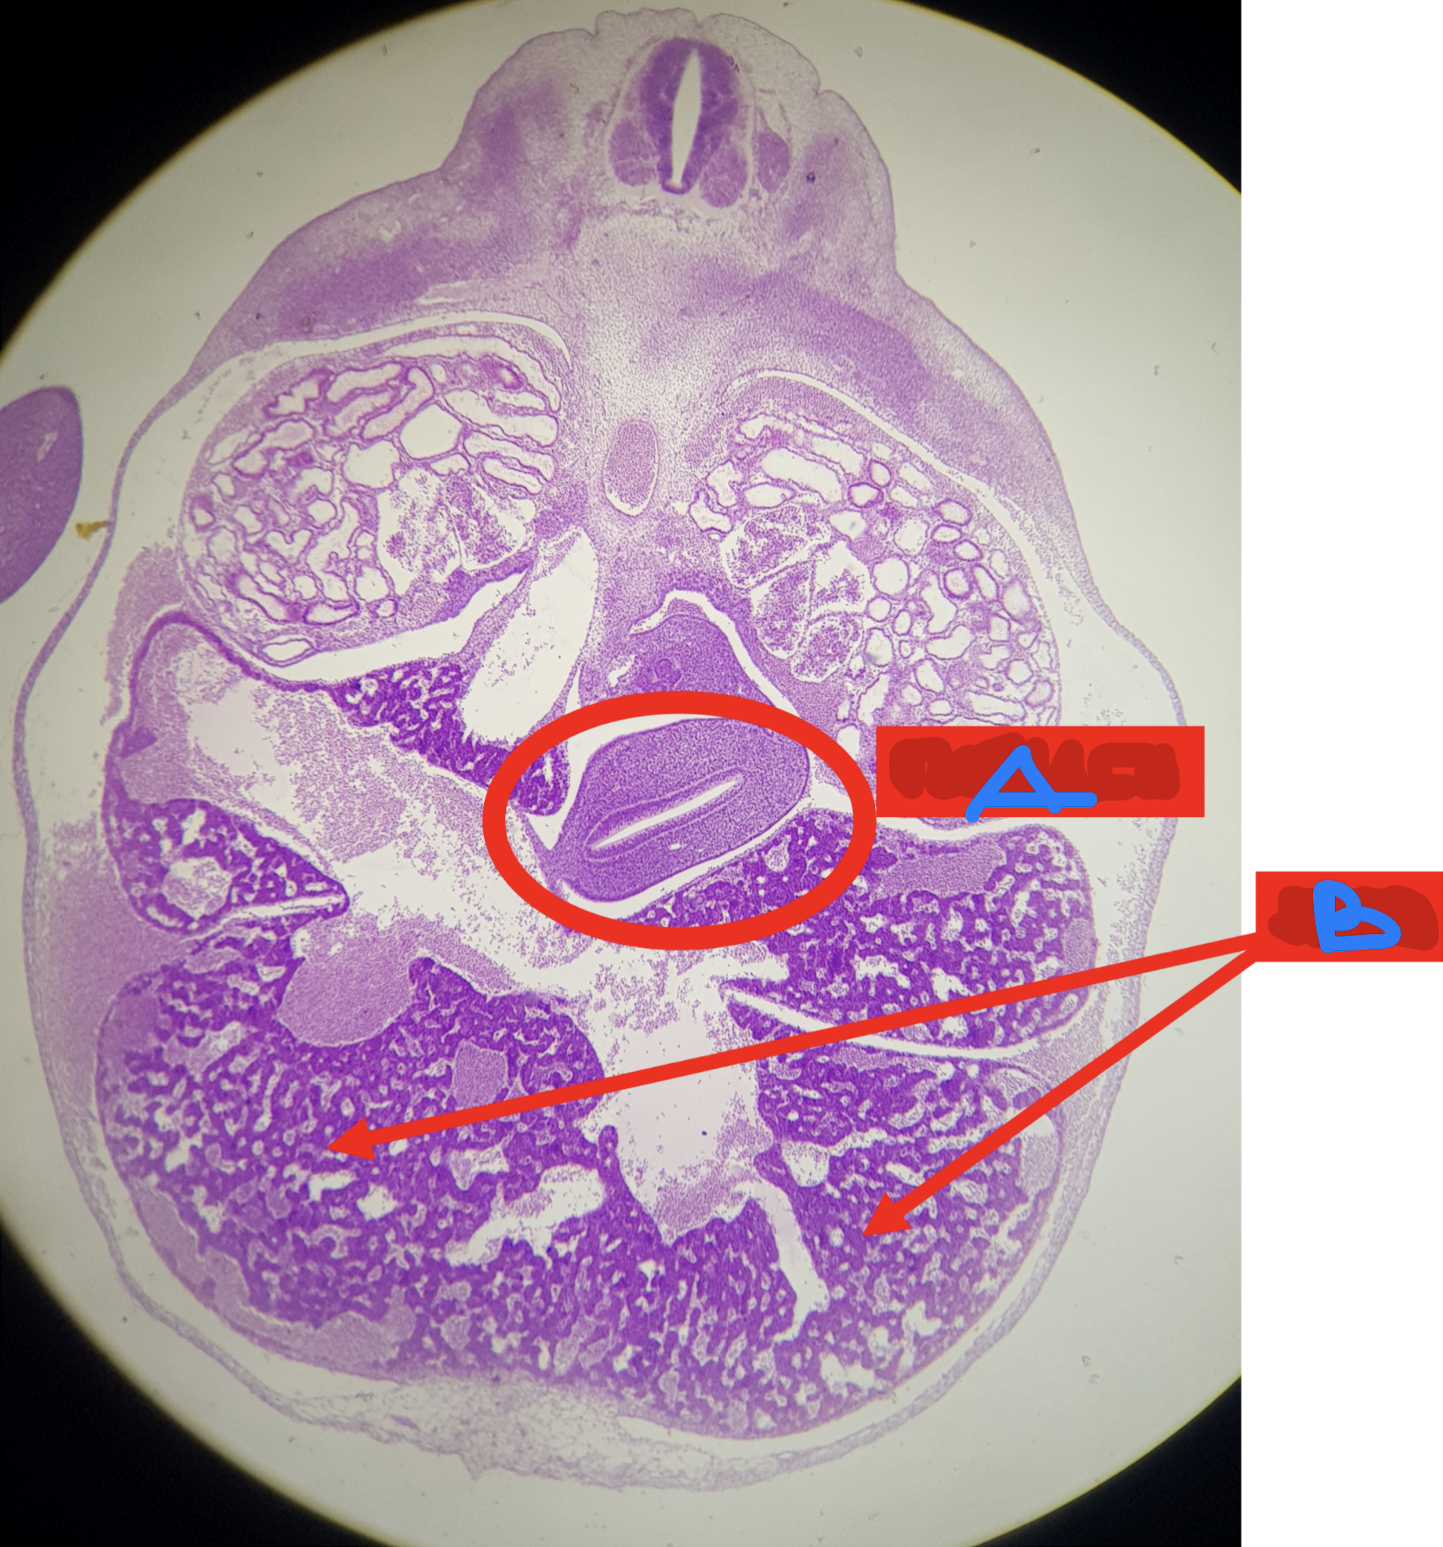

A: cloaca

B: urorectal septum

C: urogenital canal/sinus

D: anal canal (anorectal canal)

Identify the structure